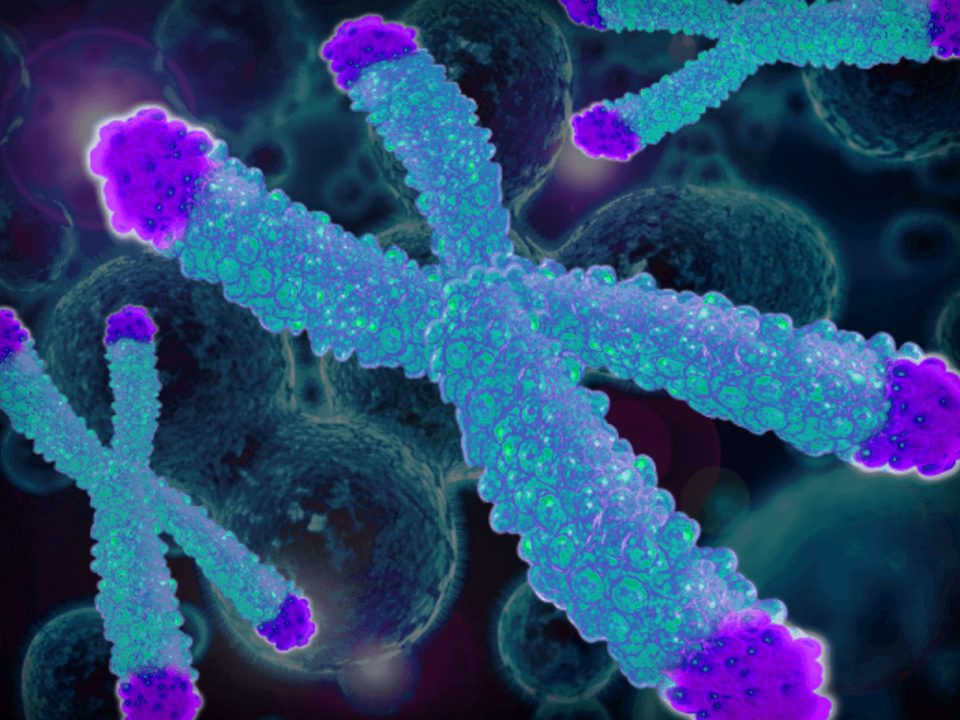

Telomeres consist of repeat DNA sequences located at the terminal portion of chromosomes that shorten during mitosis, protecting the tips of chromosomes. During chronic degenerative conditions associated with high cell replication rate, progressive telomere attrition is accentuated, favoring senescence and genomic instability. Several lines of evidence suggest that this process is involved in liver disease progression: (a) telomere shortening and alterations in the expression of proteins protecting the telomere are associated with cirrhosis and hepatocellular carcinoma; (b) advanced liver damage is a feature of a spectrum of genetic diseases impairing telomere function, and inactivating germline mutations in the telomerase complex (including human Telomerase Reverse Transcriptase (hTERT) and human Telomerase RNA Component (hTERC)) are enriched in cirrhotic patients independently of the etiology; and (c) experimental models suggest that telomerase protects from liver fibrosis progression [17].

Genetic data indicate that NAFLD is commonly observed in patients with telomeropathies, suggesting that steatosis may either be a consequence of hepatocellular senescence, as also observed in animal models, or a trigger for liver disease progression [17]. Fibrosis stage and liver disease progression are also strictly linked to cell senescence. Consistently, hepatocyte expression of p21, playing a pivotal role in the induction and maintenance of cellular senescence, was associated with fibrosis stage in NAFLD and increase liver related morbidity and mortality [18]

In humans, telomeres consist of thousands copies of six base repeats (TTAGGG) located at the extremities of the chromosomes that protect chromosomes tips from end-to-end fusion, rearrangement and translocation. Telomere length is progressively shortened at each mitosis, due to the inability of the DNA polymerase complex to replicate the very 5′ end of the lagging strand (attrition). For this reason, telomere shortening may function as a “mitotic clock” to sense somatic cells aging. When telomeres become critically short, a DNA-damage program is activated, leading to apoptosis or cell senescence. On the contrary, immortal cells (cancer, stem and germ cells) constitutionally express telomerase, a ribonuclear enzymatic complex associated with telomeres that is responsible for stabilizing telomere length by synthesizing new DNA sequences and adding them to the end of the chromosomes during DNA replication [17]. Telomerase comprises two essential components: Telomerase reverse transcriptase (hTERT) and its RNA template, the telomerase RNA component (hTERC). Dyskerin complex binds to hTERC, in order to protect it and to stabilize the telomerase complex. It includes four nucleolar proteins: Dyskerin (DKC1) and Nucleolar protein family A member 1, 2 and 3 (NOLA1-NOLA2-NOLA3). Besides telomerase, the Shelterin complex, which binds specifically to telomeres, plays a fundamental role in the protection of chromosome ends facilitating telomerase-based telomere elongation. It is composed of six core proteins: the telomeric repeat binding factors 1 and 2 (TRF1-TRF2) that bind telomeric double strand DNA, the protection of telomeres 1 (POT1), which binds the 3′ telomeric region of single strand DNA avoiding the degradation by nuclease, and the TRF-1 interacting protein 2 (TIN2), the POT1-TIN2 organizing protein (TPP1) and the repressor/activator protein 1 (RAP1), that interact with the other proteins bound to telomere stabilizing the complex (Figure 2; [17, 21]). Mutations of proteins involved in maintenance and repair of telomeres are responsible for telomeropathies [19]: a spectrum of progressive genetic diseases exemplified in the most severe cases by dyskeratosis congenita (DKC), whose common autosomal recessive form is caused by mutations in DKC1.

They are degenerative and age-dependent diseases, characterized by premature senescence of the stem cell compartment, determining increased risk of organ failure and cancer, with possible involvement of the hematopoietic compartment, lungs, mucous membranes, skin, and also the liver. Consistently, loss-of-function mutations in hTERT and hTERC may cause a spectrum of familial liver diseases [20]. Telomere length is a strong hereditable tract and telomere shortening is accentuated in chronic degenerative condition associated with high cell replication rate. Thus, involvement of telomeres and telomerase mutations seems to be important in predisposition to liver disease progression towards hepatocellular carcinoma (HCC). Indeed, the incidence of HCC increases with age, and, in particular, in nonalcoholic fatty liver disease (NAFLD), where there is a strong aggregation of familial cases [17,20].

Conversely, reactivation of telomerase occurs during hepatocarcinogenesis, allowing the immortalization of the neoplastic clone. The role of telomere attrition may be particularly relevant in the progression of nonalcoholic fatty liver, an emerging cause of advanced liver disease. Modulation of telomerase or shelterins may be exploited to prevent liver disease progression, and to define specific treatments for different stages of liver disease [17].

The role of ageing in liver fibrosis progression has been largely demonstrated, and older age and duration of liver disease remain the major and more validated risk factors for liver disease progression, together with male gender and alcohol abuse [22, 23, 24].

Cellular ageing is generally referred to as replicative senescence, a condition strictly linked to telomerase and telomere biology. Indeed, telomere shortening limited the replicative capacity of cells and the number of cells participating in tissue regeneration. Thus, the regenerative potential of an organ depends on the size of the population of cells with sufficient telomere reserves required for cell proliferation. Consistently, in chronic disease associated with tissue regeneration, such as cirrhosis, an elevated regenerative pressure is generated on the proliferating subpopulation of cells, which undergoes several rounds of cell division that, in turn, accelerate the rate of telomere shortening [17]. When telomeres become critically short, a DNA damage program is activated, leading to cell senescence or apoptosis (due to the Hayflick limit), further reducing the number of cell with regenerative capacity. In response to cellular stress, often resulting in DNA damage, proliferating cells can initiate a program that leads to a permanent cell cycle arrest termed cellular senescence. The short-term induction of cell senescence has beneficial roles in tumor suppression, wound healing and possibly embryonic development (Fig. 3). However, the long-term presence of senescent cells in tissues has the potential to promote age-related disease and cancer in a cell in non-autonomous manner[In response to cellular stress, often resulting in DNA damage, proliferating cells can initiate a program that leads to a permanent cell cycle arrest termed cellular senescence. The short-term induction of cell senescence has beneficial roles in tumor suppression, wound healing and possibly embryonic development (Fig. 3) [25]. However, the long-term presence of senescent cells in tissues has the potential to promote age-related disease and cancer in a cell in non-autonomous manner. In this review, we discuss the various triggers and mechanisms of cell senescence, the physiological and pathological consequences of the senescence program, the ability of senescent cells to interact with immune cells and provide possible explanations for why senescent cells may persist in tissues [25].

Several lines of evidence correlate shortened telomeres with liver fibrosis. Kitada et al. [26] first described a progressive reduction of telomere length during liver disease progression. Urabe et al. [27] confirmed these data and described telomerase re-activation in poorly differentiated HCC, consistently with an increase of telomere length compared to those well differentiated. In the normal liver, progressive telomere shortening has been correlated with age. Consistently, reduction of telomere length in cirrhotic tissue was more marked in patients who developed cirrhosis at younger age [17]. Additionally, reduction of telomere length is considered a hallmark of cirrhotic tissue independently of the etiology of liver disease (e.g., viral hepatitis, autoimmune hepatitis, alcohol abuse…) [28].

Thus, excessive telomere shortening, caused either by telomerase gene mutations or acquired factors, may impair the hepatocyte regenerative ability in response to chronic injury, facilitating fibrosis progression. A causal role of telomere shortening in fibrosis progression has been experimentally demonstrated in telomerase deficient mice. After three generations, these mice developed shortened telomeres and displayed diminished capacity for liver regeneration, and with accelerated development of cirrhosis after liver injury. On the contrary, overexpression of TERT activity improved liver function and protected mice from development of hepatic steatosis and fibrosis [17].

Consistently, shortened telomere length in cirrhotic patients was correlated with the expression of known markers of cellular senescence, such as β-galactosidase, p16, p21 and p53 not only in hepatocytes but also in non-parenchymal cells, such as biliary cells. The p53 protein represents the key regulator point for various signaling pathways of senescence: p53 phosphorylation and consequent activation inhibits cell division primarily inducing p21 expression, which, in turn, activates pRb through inhibition of a cyclin-dependent kinase (Cdk) complex. The activated pRb inhibits the transcription of E2F target genes that are required for cell cycle progression. pRB can alternatively be activated by p16, another Cdk inhibitor, that typically accumulates in senescent cells [17].

Cellular senescence may have a dual role in liver disease: in a first phase, it seems to contribute to liver impairment by reducing the hepatocytes and progenitor cell population, while, in a second phase, the subsequent senescence of HSC (epatic stellate cells) due to long-standing activation of fibrogenesis may protect from further fibrosis progression. In particular, progression of human fibrosis is often characterized by a state of chronic inflammation that results in a condition of cell death and tissue regeneration, involving also a massive expansion of hepatic progenitor cells in order to restore the lost hepatocytes. Ductular reaction typical of this condition has been shown to produce chemotactic stimuli for induction of inflammatory cells and activation of pro-fibrotic hepatic stellate cells (HSC). Moreover, due to the epithelial to mesenchymal transition, progenitors and biliary epithelial cells may provide a portion of myofibroblasts, contributing to fibrosis progression [17]. When the wound is filled, the activated HSC undergo apoptosis or cellular senescence and consequently are eliminated by immune cells. In this way, HSC induce the recruitment of other immune cells at the site of tissue injury that, in turn, help in arresting liver fibrosis progression. However, it has recently been shown that later, senescent HSC may favor HCC development by secreting pro-carcinogenic mediators (the senescence associated secretory program: SASP) [17]. In studies has been shown that in obese people hepatic tissue was characterized by signs of accelerated aging.